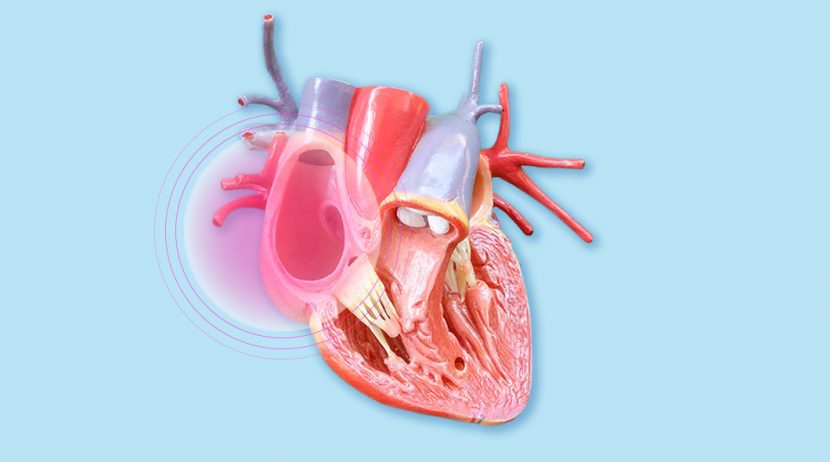

O coração é um músculo. Um órgão do tamanho do nosso punho, que está ligeiramente desviado para a esquerda. É composto por quatro cavidades, duas no lado esquerdo e duas no lado direito, separadas por uma parede de músculo chamada septo. Às cavidades superiores, de menor tamanho, dá-se o nome de aurículas.

Veja-as aqui através de uma imagem bem clara.